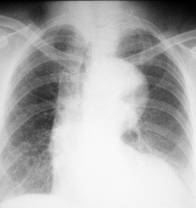

STENOZA MITRALĂ

- micsorarea butonului aortic - datorita reducerii debitului sanguin în aorta, a rotatiei cordului spre stânga si dilatarii arterei pulmonare

- rectitudinea sau bombarea arcului mijlociu - dilatarea arterei pulmonare

- micsorarea arcului inferior stâng

- dilatarea AS Prin examinarea esofagului cu pasta baritata se poate aprecia mai bine aceasta micsorare în grade variabile a spatiului retrocardiac (gradul I - amprenta a atriului pe conturul anterior al esofagului; gradul II - împingerea esofagului pâna la coloana vertebrala; gradul III - esofagul este împins posterior, dincolo de fata anterioara a corpilor vertebrali). Uneori atriul stâng apare în interiorul siluetei cardiace constituind conturul dublu concentric.

- hiluri de staza

- modificari în parenchim: transudatele alveolare determina aparitia de opacittati cu localizare mediopulmonara si bazala de intensitate slaba.